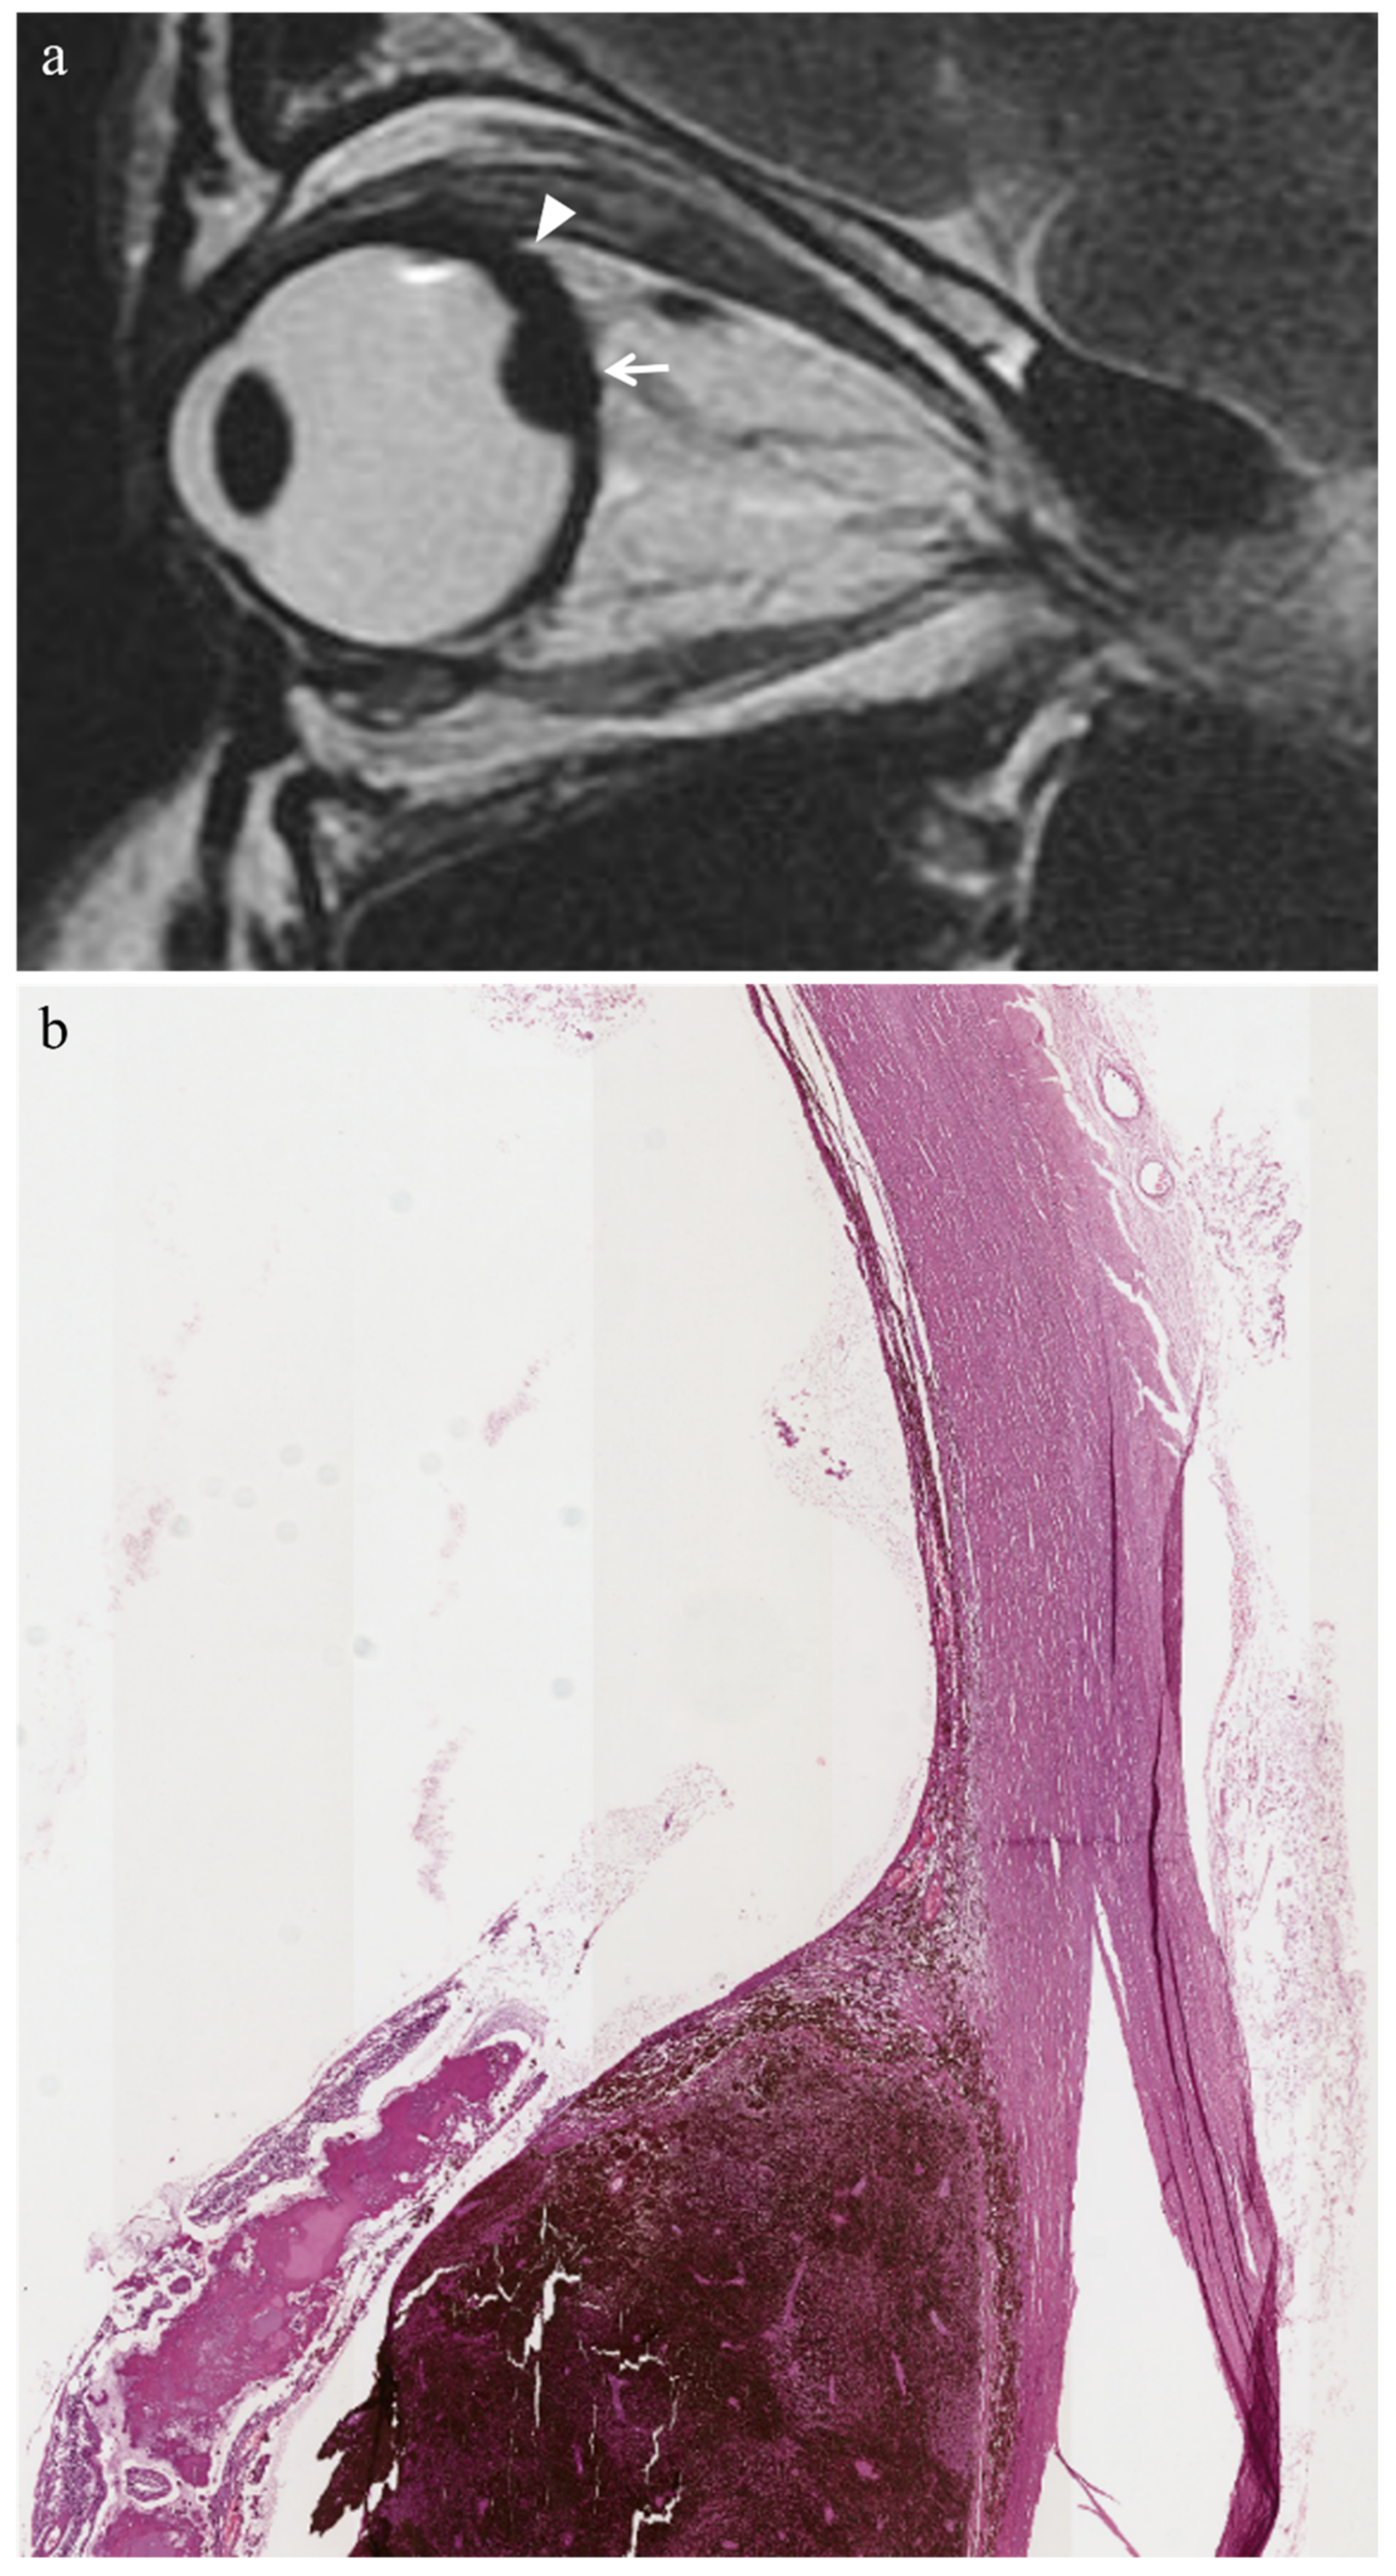

| Periocular fibrotic adhesion | ![]() Low signal | ![]() Low signal | - | - |